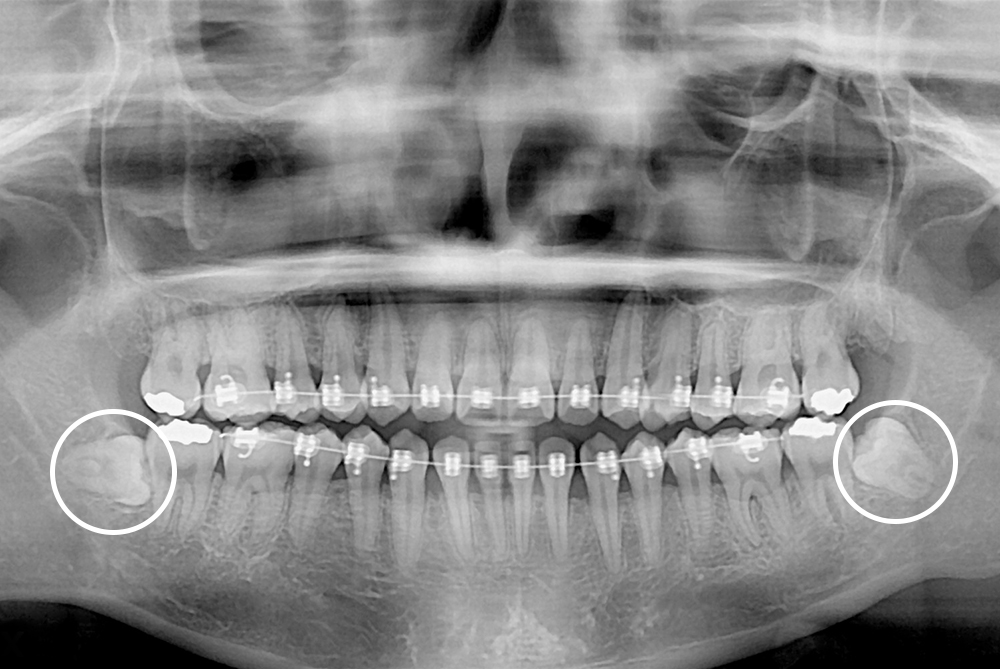

[사랑니] 매복 사랑니 발치

치료후 : 2022-07-13

세종치과는 구강악안면외과학 박사이신 원장님이 발치하는 치과입니다.